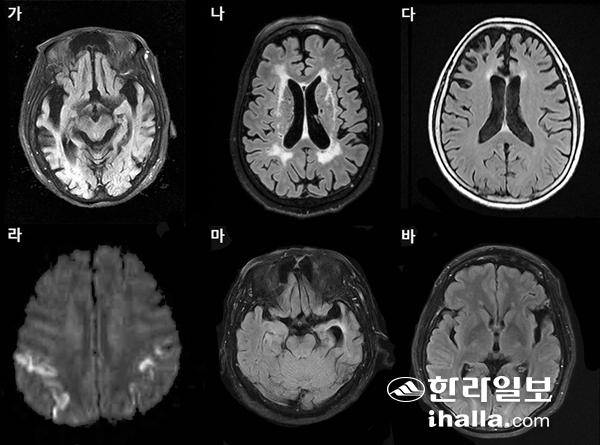

가. 알츠하이머치매 나. 혈관치매 다. 전측두엽치매(행동이상) 라. 크로이츠펠트-야콥병 마. 의미치매 (전측두엽치매 중 언어이상) 바. 비유창성 실어증(전측두엽치매 중 언어이상).